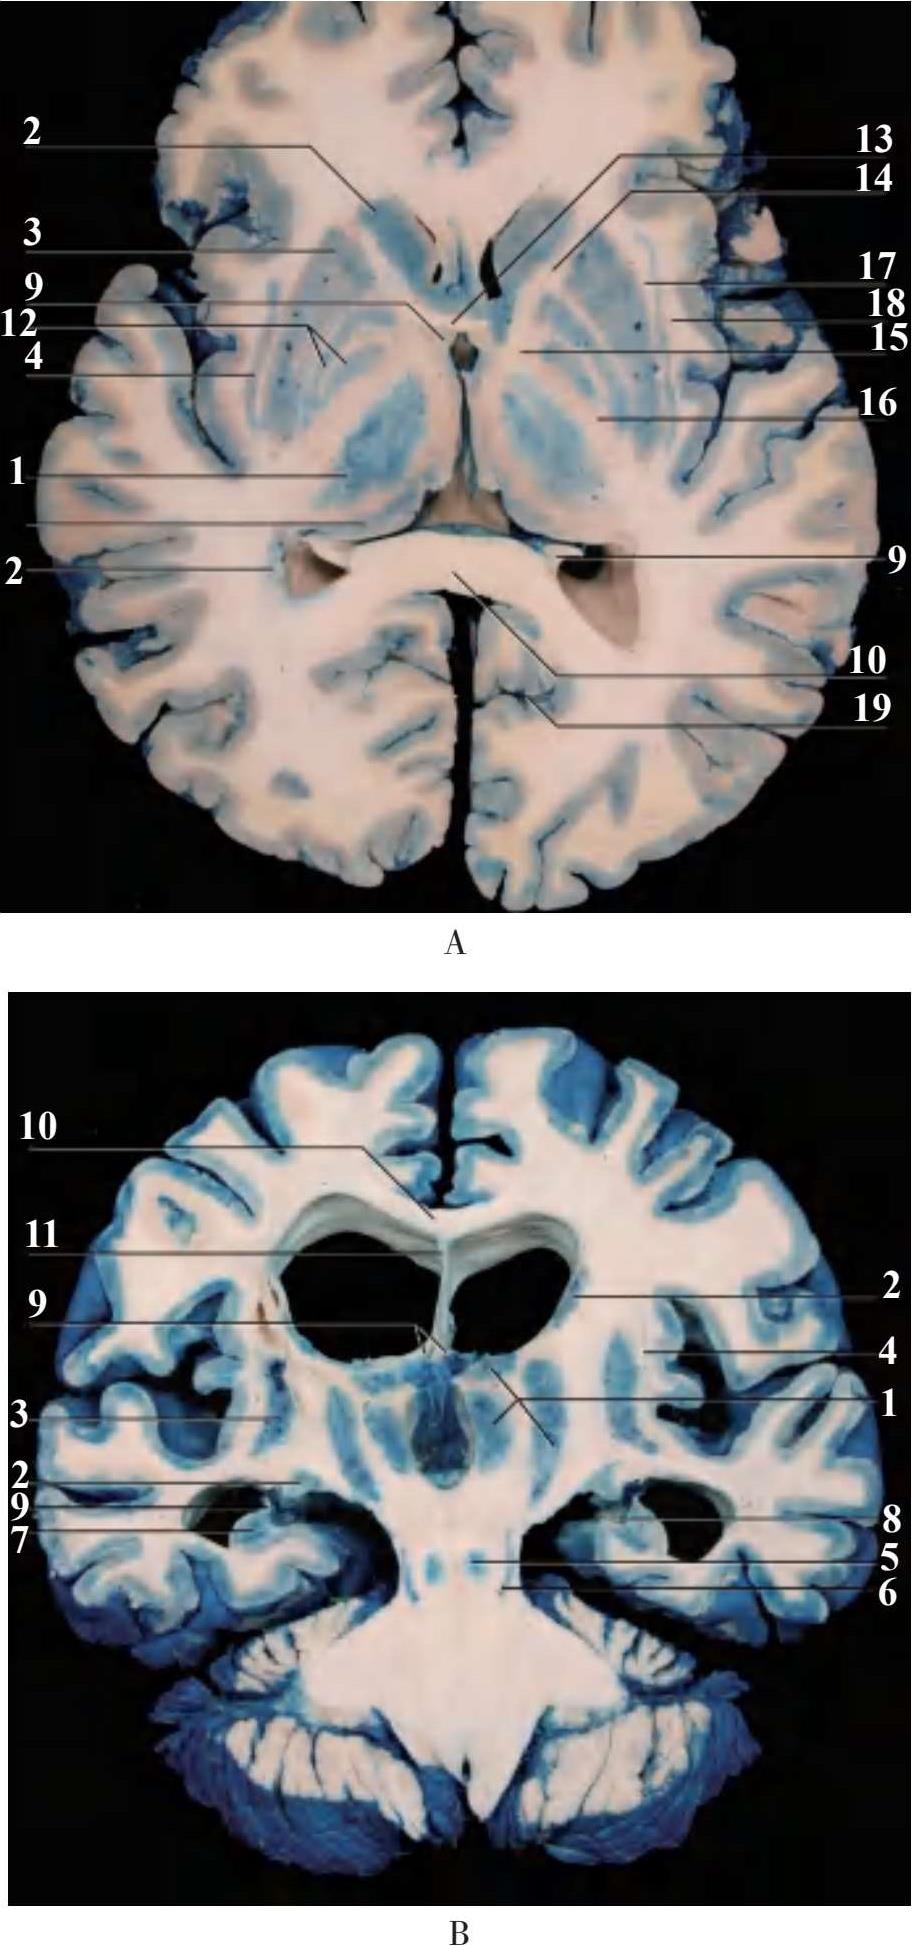

1.丘脑 thalamus;2.豆状核 lentiform nucleus;3.纹状核壳 putamen;4.屏状核 claust rum;5.红核 red nucleus;6.黑质 substantia nigra;7.海马 hippocampus;8.齿状回 dentate gyrus;9.穹隆 fornix;10.胼胝体 corpus callosum;11.透明隔transparent septum;12.苍白球 globus pallidus;13.前连合 anterior commissure;14.内囊前肢 anterior limb of internal capsule;15.内囊膝 genu of internal capsule;16.内囊后肢 posterior limb of internal capsule;17.外囊 external capsule;18.最外囊exterme capsule;19.距状沟 calcarine sulcus

图2-7 端脑内部主要结构